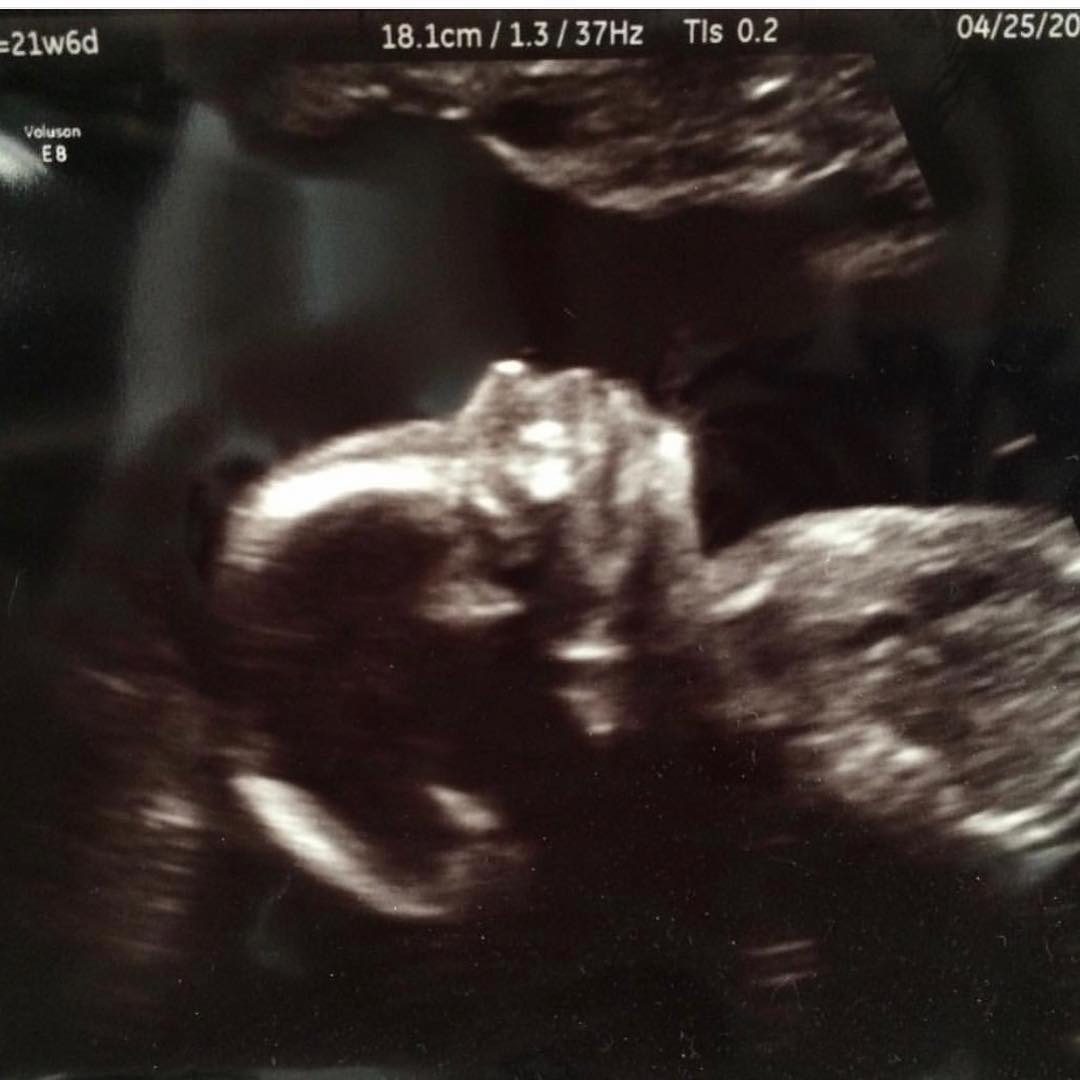

“I can’t wait to kiss this little face. This was her 20 week ultrasound where we got to see her perfectly healthy anatomy. As soon as the ultra sound was complete the doctor asked if we wanted to terminate. Terminate??? We just saw a perfect little human who happens to come with an extra chromosome. Oh how I wish we lived in a world that valued all human life.” – Amy